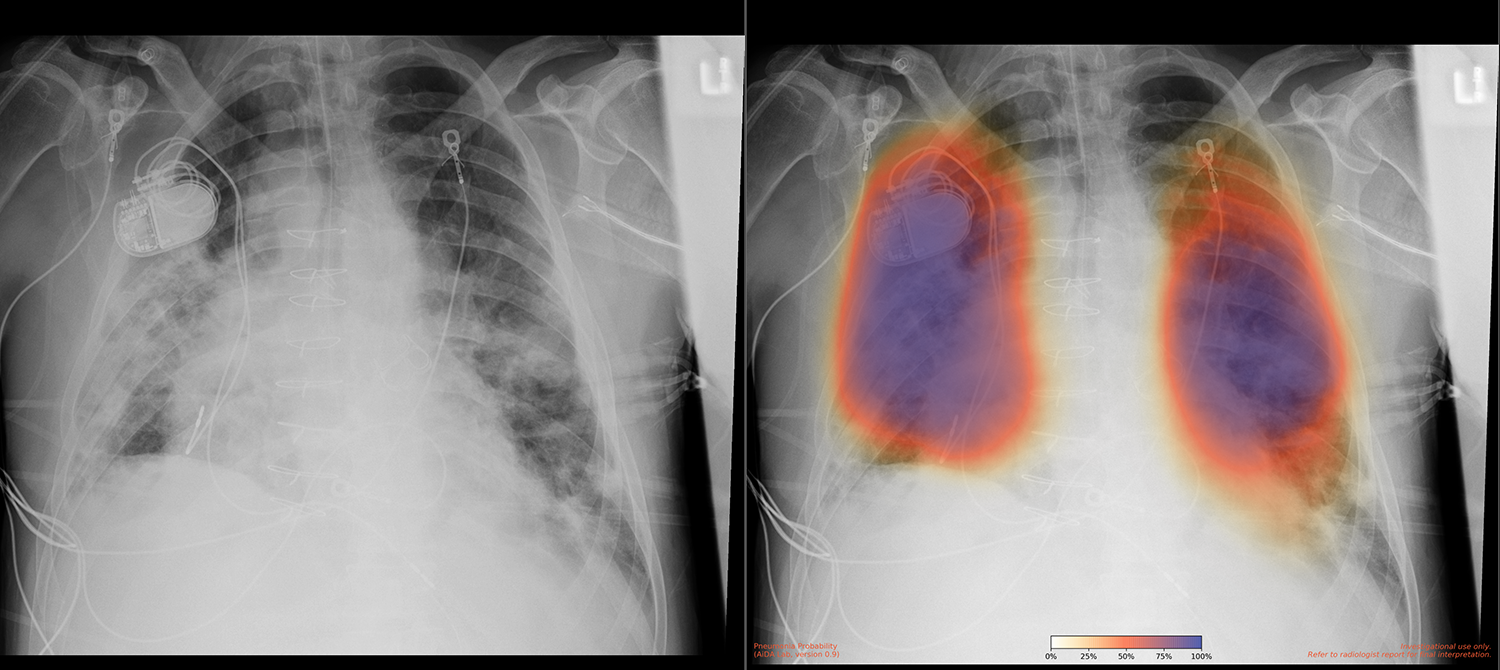

UC San Diego Health is among the top 15 research universities worldwide. The UC San Diego School of Medicine conducts hundreds of clinical trials each year, and the UCSD Health Services Research Center specializes in the collection and analysis of health outcomes data to support research. In 2018, a team from UC San Diego Health, led by Dr. Albert Hsiao, associate professor of radiology at the UC San Diego School of Medicine, developed a way to use machine learning to detect pneumonia in X-ray images. “We created a probability map with color coding that indicated how uncertain or certain a pneumonia was,” says Dr. Brian Hurt, a resident physician on Dr. Hsiao’s team. According to Dr. Hsiao, “What people typically do is create a model that gives a simple yes or no output, indicating whether it’s pneumonia or not pneumonia. But we felt that producing an image was important to highlight where abnormalities are.” The team published a paper on these results in early 2020.

The goal was to implement a system that could take in X-rays from a clinical setting, run the model on them, and return results quickly to assist with diagnosis. “A lot of models created in labs like ours are potentially promising but not very useful without actually building them into the clinical workflow,” says Dr. Hsiao. Such an implementation would potentially affect the diagnosis, treatment, and outcomes of COVID-19 patients. “The findings of COVID-19 pneumonia are basically the same as those of any other viral pneumonia,” says Dr. Hsiao. “The model that Brian trained performs well in this population because it’s a good model for detecting pneumonia in general.” The model was useful in two ways. First, if it detects pneumonia in an X-ray image, it prompts a test or retest in the event of a previous—possibly false—negative test result. Second, in patients with known infection, finding pneumonia on an X-ray could indicate the illness’s severity and prognosis, informing treatments.

The UC San Diego Health research team had already set up the model to take in images and return them with a color-coded overlay. It only needed a cloud solution that could connect to the clinical imaging system to receive the images and output them directly into the patients’ files, making the images convenient for medical professionals to access and view. Because the team had already created HIPAA-compliant environments on AWS, it was able to get the project up and running in a mere 10 days. “The first day it was running on AWS, the model processed around 400 X-rays with very few glitches,” says Dr. Hogarth. In the next 6 months after implementation, the model processed over 65,000 X-rays, each in 3–4 minutes.

A recent paper published by the Journal of the American College of Emergency Physicians Open indicated that implementing this model has impacted clinical decision-making 20 percent of the time. “There are very few things that we know of that really impact clinical decision-making to that extent,” says Dr. Hsiao. The model’s initial accuracy was 86 percent, and the team will soon deploy an even more accurate version that accounts for pneumonia cases often missed when located behind the heart.